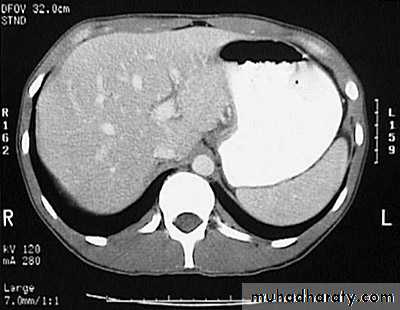

Hydatid cystAppear as large oval hypo dense area density of fluid with well defined margin , sometime at their periphery multiple flecks of calcification are seen at their periphery .

Hydatid cyst with daughter cyst , appear as multiple hypo densities rounded area within the main loculi with multiple rim of

calcification

Hydatid cyst within the liver